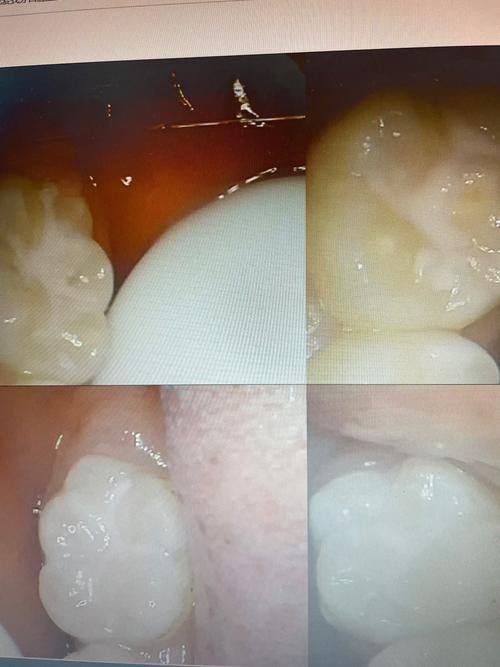

19. 儿童窝沟封闭:100 - 300元